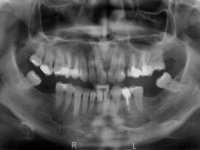

The patient presented a superior dental midline deviation of about 6 mm to the left. Due to the absence of the maxillary left central incisor, the adjacent teeth drifted into this area, limiting the available space for a prosthodontic rehabilitation. There was a significant dental negative disharmony in the maxillary arch as a result of the absence of the left central incisor, absence of the first premolar with a residual space, significant crown reduction of the right second premolar, migration of the posterior teeth into the unoccupied spaces and an upper right and left molar mesialization with a Class II molar relationship. Both left and right canine showed a Class II dental relationship in the maximum intercuspidation position. The patient had a medium lip line smile, a medium thick gingival biotype, presented an adequate oral hygiene without periodontal disease, and no para-functional habits. Radiographic analysis shows a significant inclination of axis of the teeth 11 and 22 with a space available between the apical part of the roots. A cephalometric analysis was made in order to explore the hypothesis of achieving the necessary space to place an implant and a crown in tooth place 21. Finally, the morphology of the residual bone in the anterior region of the maxilla was evaluated with a cone –beam CT scan, revealing a loss of the buccal bone wall dimensions.